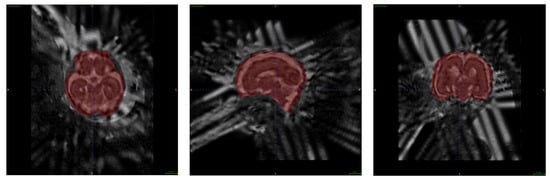

Images obtained during fetal MR exams are frequently corrupted by motion artifacts resulting from the unpredictable motion of the fetus, as well as that of the pregnant patient. When significant motion artifacts are visible within the acquired 2D MR images, the MR technologist would usually repeat the acquisition of the motion-corrupted series. Therefore, fetal MR exams often contain multiple 2D series acquired within the same anatomic planes. As step 1, the regions representing the fetus’ brain were extracted from all the T2-weighted 2D HASTE series. Figure 3 shows the outputs for fetal brain extraction, in sagittal, coronal, and axial series.

Figure 3. An example of fetal brain extraction and segmentation in all three anatomic orientations. (a) is axial, (b) is sagittal, and (c) is coronal for fetal brain segmentation.